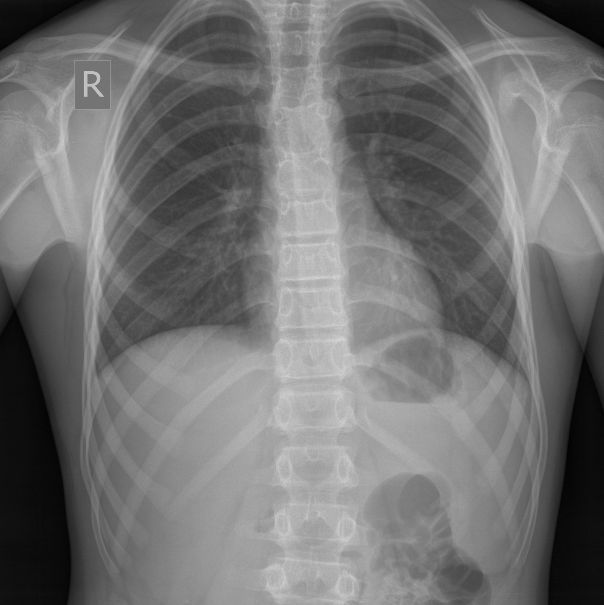

После УЗИ - сделал рентген, изменения в ребре есть, но в глаза не бросаются

Diagnosis of Ewing's Sarcoma is suspected